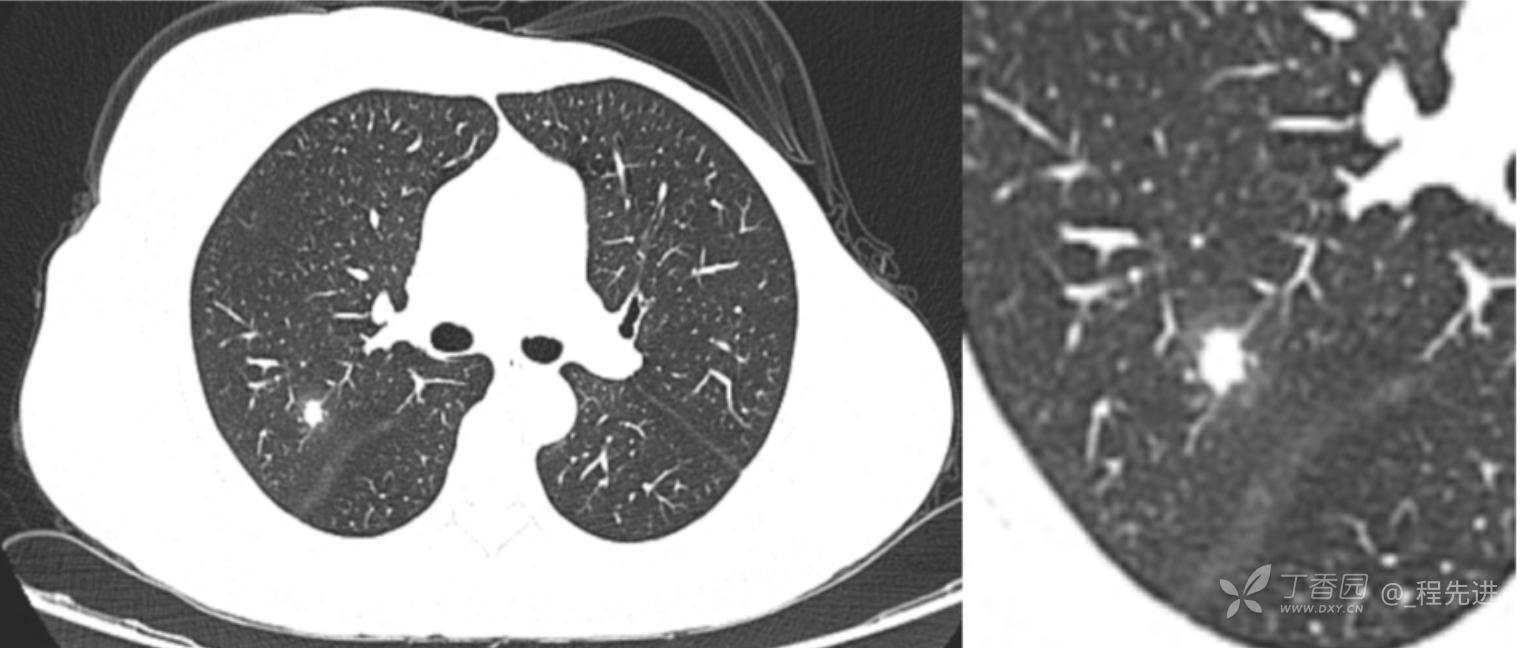

患者性别:女

患者年龄:52岁

简要病史:体检发现右肺上叶结节

既往史:左乳腺癌术后,化疗后